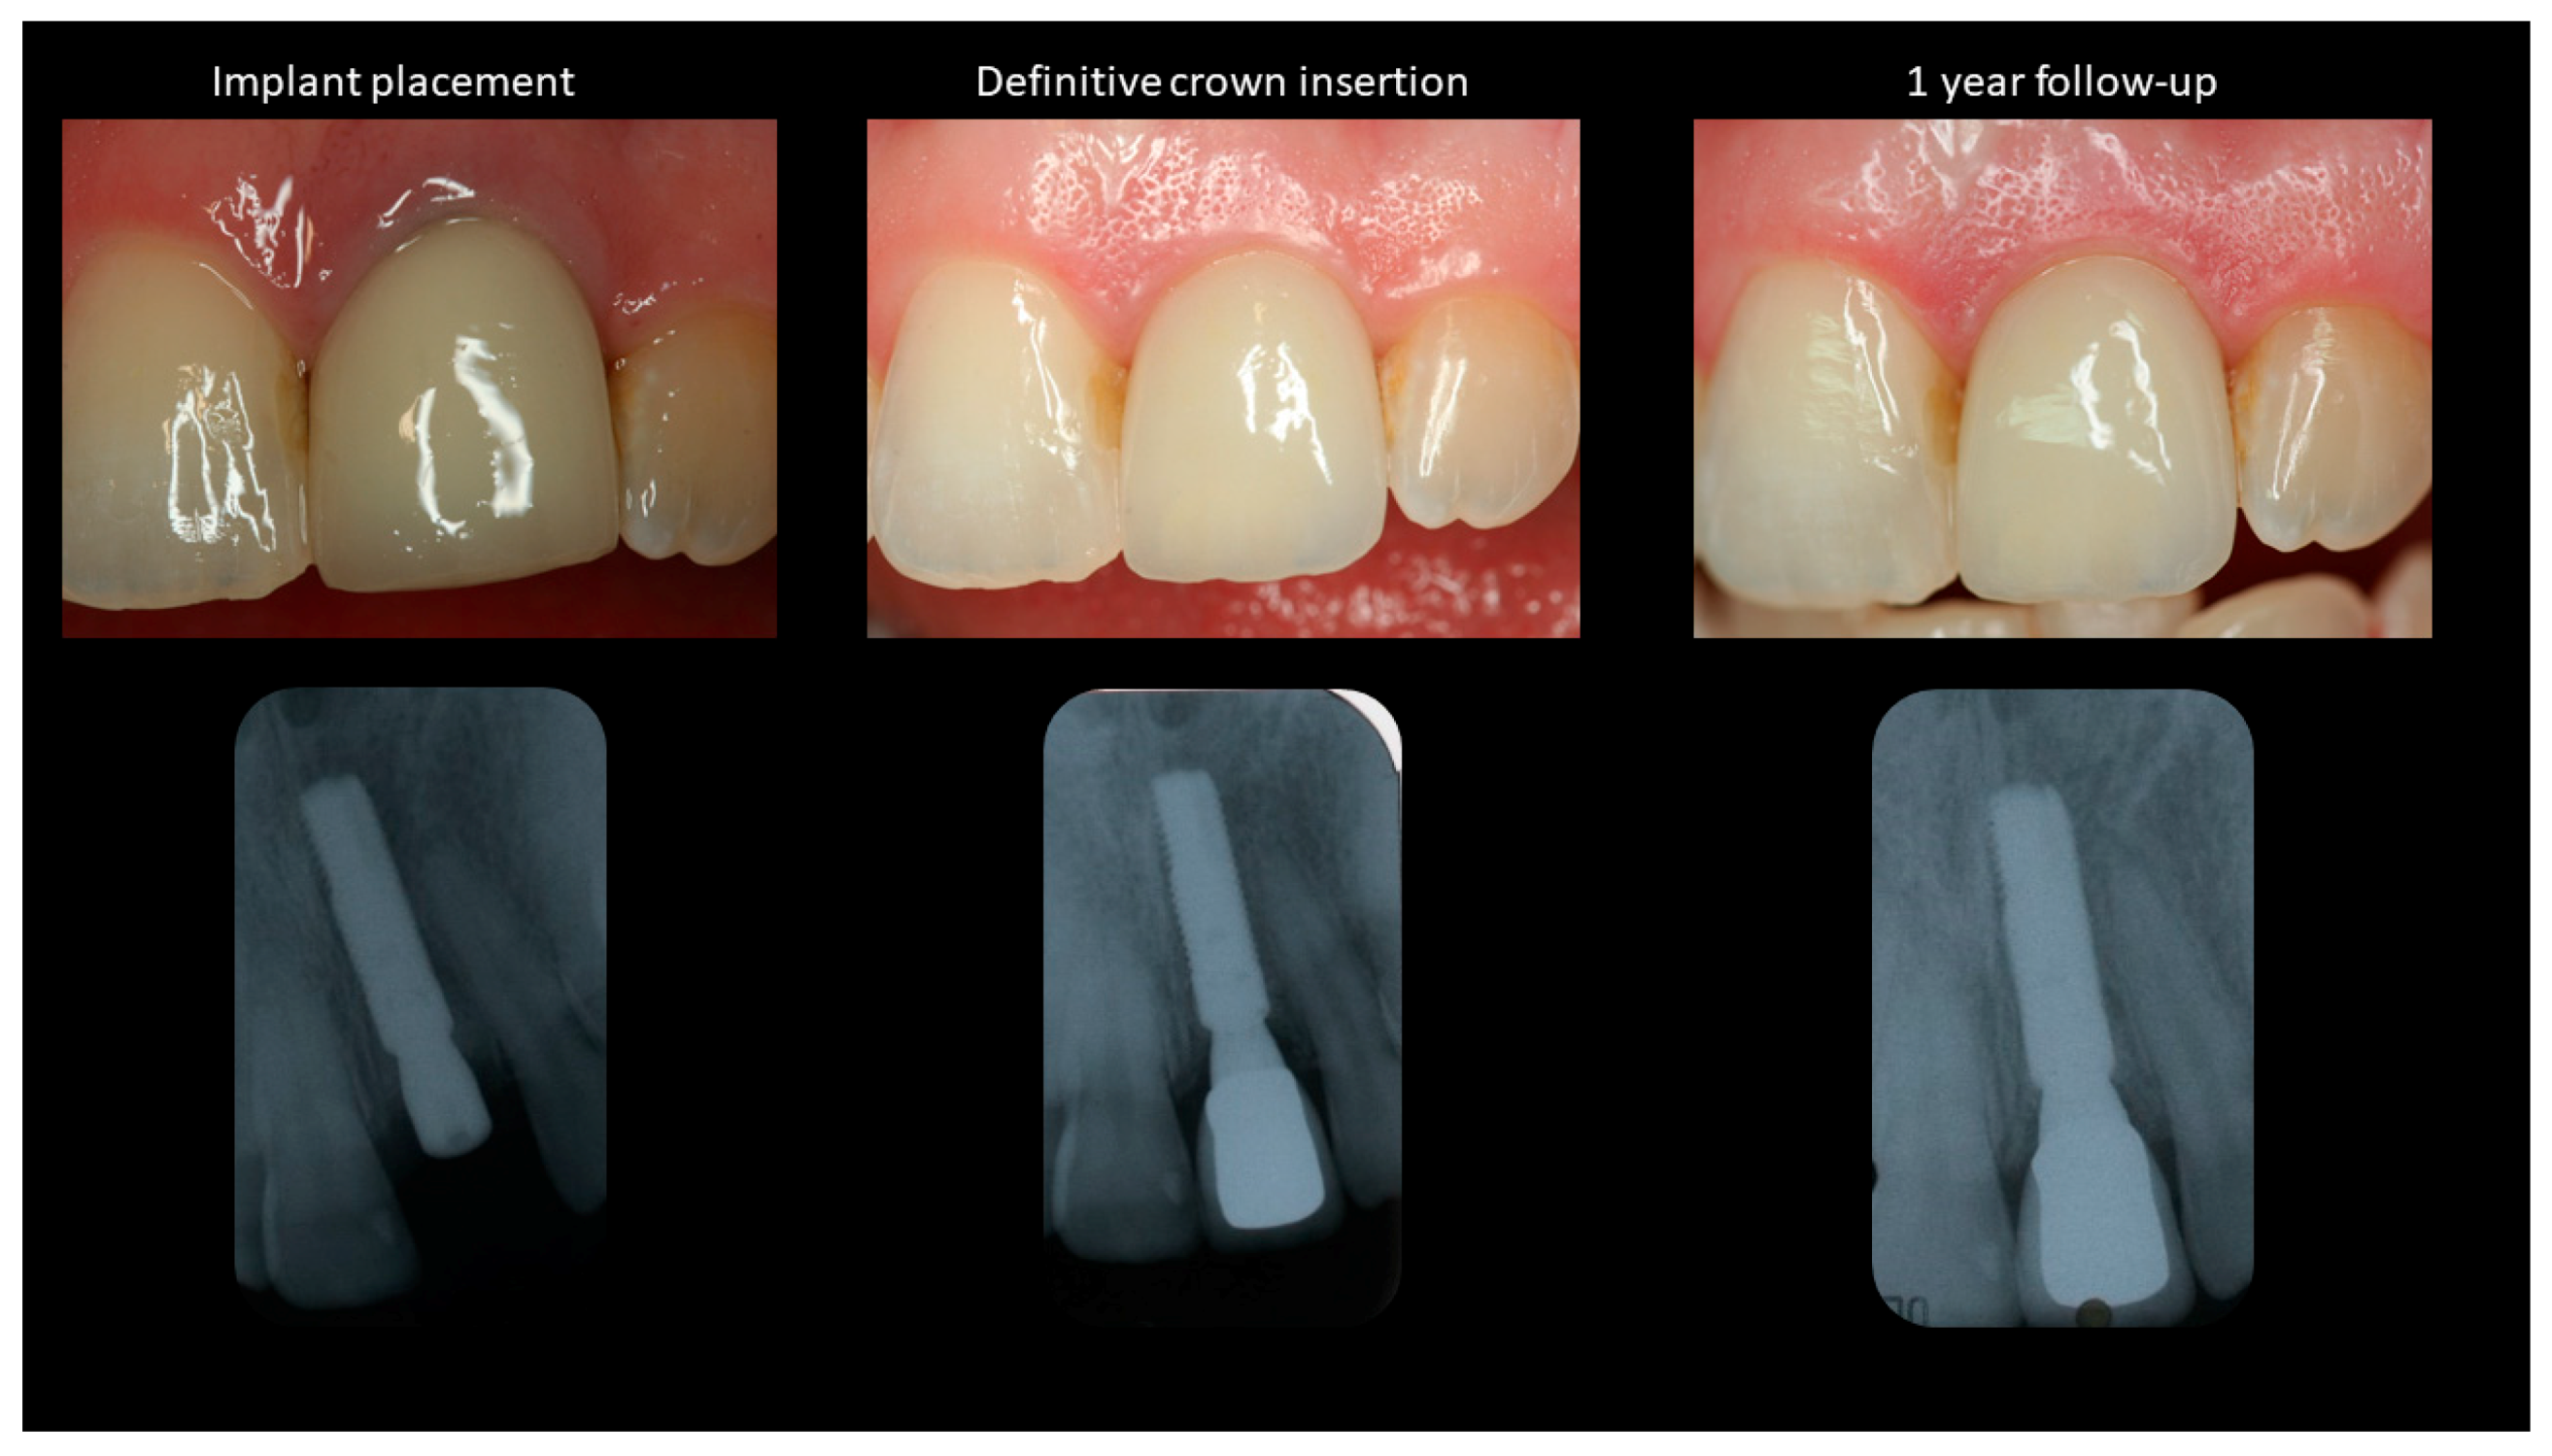

At each follow-up appointment, peri-implant soft and hard tissues were checked clinically and with the help of radiographs (Figure 2 and Figure 3). Intraoral radiographs were taken with a paralleling technique after implant placement and the various follow-up time-points. These images were imported to Image J software (Image J 1.43u, NIH, Bethesda, Maryland) to evaluate the changes in peri-implant bone levels. The implant length and the inter-thread distance was used for image calibration and the implant shoulder was used as a reference to evaluate the changes in bone levels over time.

Figure 2.

Peri-implant soft and hard tissue levels at implant placement, crown insertion and 1-year follow-up.

Intraoral photographs were taken with the help of a DSLR camera (Cannon 1300D, Cannon Inc., Tokyo, Japan) at a fixed angle and magnification ratio to evaluate the soft tissue changes around the implant (Figure 2 and Figure 3). A periodontal probe with standardized markings was placed on the adjacent tooth to help in image calibration. The images were imported to Image J where the incisal edges of the adjacent teeth were used to draw a reference line based on which the changes in the papillae and midfacial soft tissue levels were calculated, as described previously [5].

Figure 2 and Figure 3 show the clinical photographs and radiographs from baseline (T0) to the final follow-up (T5). A minor gain in the midfacial mucosal margin was observed between implant placement and connection of the definitive crown (Table 1). The midfacial mucosa remained stable after the insertion of the crown to the 10-year follow-up. Mesial and distal papilla levels remained stable between the T0–T4 time points. Although no changes were seen in the distal papilla, a slight change was observed in the mesial papillary level between T4–T5 (Table 1). A slight improvement was observed in the aesthetic outcomes as measured with the help of PES. The overall PES improved from 10 at T0 to 11 at T5.

Evaluation of the bone levels around the implant revealed an overall gain of 0.7 mm on the mesial and distal aspects between implant placement and 10-year follow-up (Table 1).